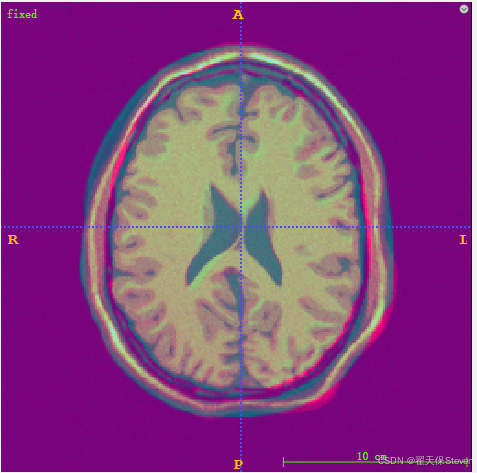

6)如上图所示,右上角箭头点一下,有一个Overlays,点击里面是moving,再后面一层有一个 opacity滑动条,往左滑到头就是fixed,往右滑到头就是moving,通过滑动可以实现直观观察。如下图所示,就是两张图分别权重为0.5的样子。

7)如果两张图像都是灰度图不太明显,可以将两张图的Color Map改一下,也是箭头点一下,点Color Map,fixed选择Hot,moving选择Cool。如下所示。

8)再次融合,就能看出差异了。